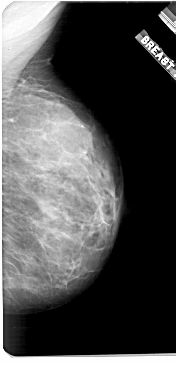

A_1921_1.LEFT_CC

LEFT_CC LINES 5011 PIXELS_PER_LINE 2851 BITS_PER_PIXEL 12 RESOLUTION 43.5 OVERLAY